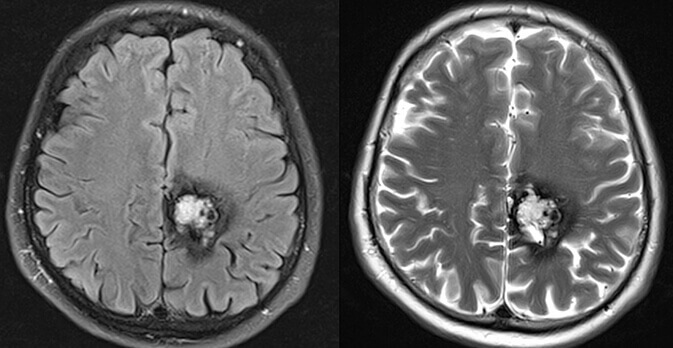

Είναι καλοήθεις δυσπλασίες στο φλεβικό σκέλος, με σηραγγώδεις φλεβικές λιμνάσεις, χωρίς αρτηριοφλεβώδη επικοινωνία. Μπορεί να είναι μονήρεις (σποραδική μορφή) ή πολλαπλές. Στην τελευταία περίπτωση είναι συνήθως οικογενείς και κληρονομούνται κατά τον αυτοσωματικό επικρατούντα χαρακτήρα (χρωμόσωματα 7q21-22(CCM1), 7p13-15(CCM2) και 3q25-27(CCM3)).

Αυξάνονται σε μέγεθος μετά από επεισόδια αιμορραγίας λόγω υποτροπιαζόντων, συρρρεόντων μικροαιματωμάτων που συμβαίνουν σε διαφορετικές χρονικές περιόδους. Εντός της βλάβης διακρίνονται αιμορραγικά στοιχεία σε διαφορετικά χρονικά στάδια (παλαιότερα και πιό πρόσφατα).